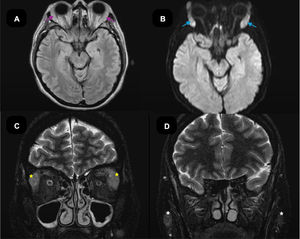

The patient met Okazaki's clinical criteria and exhibited elevated IgG4 levels. A glandular biopsy confirmed a definitive diagnosis of IgG4-RD (Table 2, see left submandibular gland biopsy), warranting treatment with prednisone 10mg once daily and methotrexate 20mg weekly. Magnetic resonance imaging (MRI) of the orbits and brain revealed diffuse enlargement of the lacrimal and parotid glands, without thickening of the extraocular muscles or masses suggestive of an orbital pseudotumor. Bilateral proptosis was present, along with nonspecific supratentorial white matter hyperintensities (Fig. 3), which were not characteristic of the disease.

Magnetic resonance imaging (MRI) of the brain and orbits. (A) Axial fluid-attenuated inversion recovery (FLAIR) sequence showing hyperintensity at the level of the lacrimal gland, indicating tissue inflammation (purple arrow). (B) Axial diffusion-weighted imaging (DWI) sequence showing active inflammation at the level of the major lacrimal gland (blue arrow). (C) Coronal T2 contrast (gadobutrol). At the level of the major lacrimal glands, a diffuse homogeneous enlargement of the bilateral lacrimal glands was observed, with restriction similar to that seen in the brain and heterogeneous enhancement with contrast medium, without thickening of the muscle bellies or masses (yellow asterisk). (D) Coronal T2 contrast (gadobutrol). Shows diffuse enlargement of both parotid glands (white asterisk).